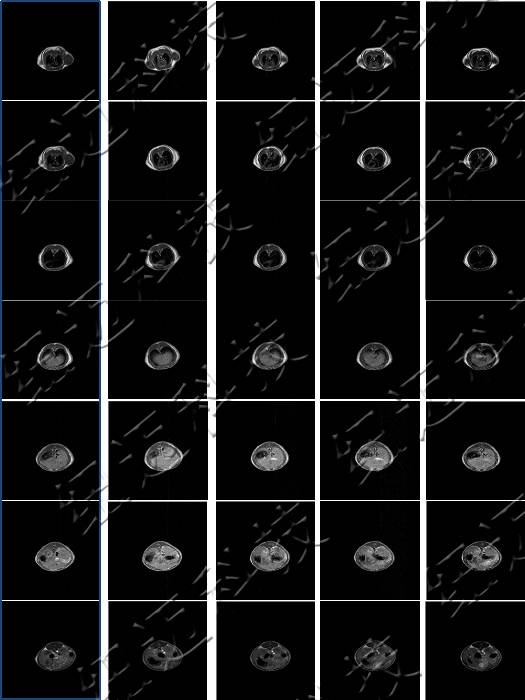

测试钆类MRI造影剂弛豫率测试以及造影剂样品的T1加权成像。

弛豫效率是MRI造影剂关键指标之一。

造影剂:通过内外界弛豫效应和磁化率效应间接地改变组织信号的强度,以增加组织或器官对比度的一类物质。

核磁共振成像(MRI)目前普遍应用于医学检测成像中,具有无辐射损伤的安全性,可任意方位断层扫描等技术灵活性,加以涵盖质子密度、弛豫、加权成像以及多参数特征的优势,已成为当代临床诊断中最有力的检测手段之一,然而临床发现某些不同组织或肿瘤组织的弛豫时间相互重叠,导致诊断困难。